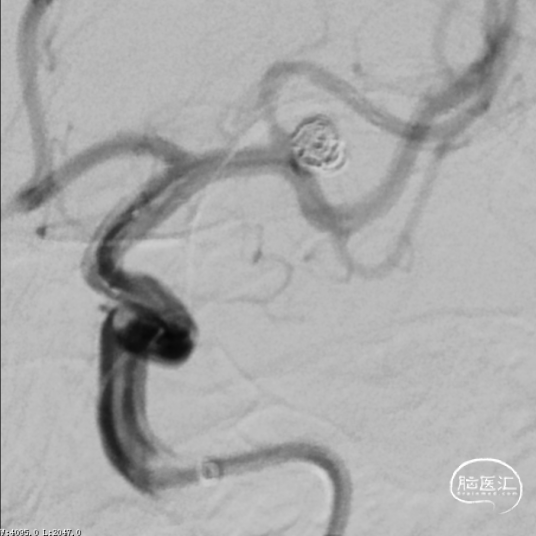

释放支架前经导引导管缓慢注入替罗非班6ml,之后持续静脉泵入,速度5ml/h。手术历时60分钟,麻醉顺利苏醒,神经系统查体:未见阳性体征。NIHSS评分:0分;Raymond分级:Ⅰ级,mRS评分:0分。术后即刻行C-arm CT头颅扫描,未见出血,动脉瘤填塞致密,支架开放良好。

术后6个月复查造影示:弹簧圈致密充填瘤体内,瘤体消失,左侧颈内动脉及大脑前、中动脉均显影良好,载瘤动脉通畅,形态和血管直径较动脉瘤栓塞前无明确变化。支架形态良好,未见移位及血栓形成。